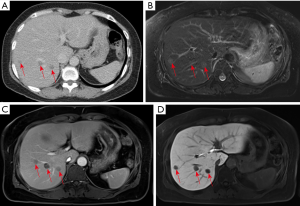

The second patient was a 58-year-old female with a history of right ovary clear cell adenocarcinoma and total abdominal hysterectomy and salpingo-oophorectomy were performed about 6 years ago. The routine follow-up imaging examinations showed no evidence of local tumor recurrence or distant metastases. The contrast-enhanced CT demonstrated multiple low attenuating lesions with peripheral enhancement in both lobes of the liver (Figure 2A) 3 years ago. The follow-up Gd-EOB-DTPA contrast-enhanced MRI revealed multiple hyperintensity nodules on the T2-weighted image (Figure 2B) with rim enhancement in the venous phase (Figure 2C) and without contrast agent uptake in the hepatobiliary phase (Figure 2D). Hepatic metastases were suspected after examinations, and FNA was performed on the nodule in segment S6 of the liver. Based on histopathology, the diagnosis was a hepatic granuloma, which was composed of epithelioid histiocytes and inflammatory cells without caseous necrosis. Then evaluation by NTM and MTB PCR kit showed positive for NTM infection and negative for MTB infection. The final diagnosis was a hepatic nontuberculous infectious granuloma, and antitubercular therapy was performed for 3 courses of treatment (21 days/1 course). In the subsequent three years of follow-up, the patient showed no significant changes of multiple hepatic granulomas and no newly developed lesions.